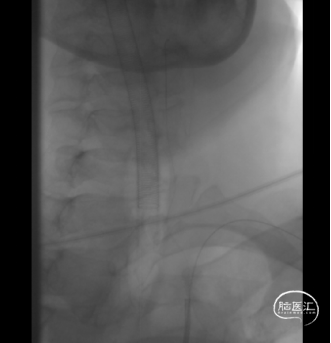

主动脉弓造影:Ⅰ型弓,右侧锁骨下动脉血管路径迂曲。

经远桡动脉入路。

术前造影提示:右椎动脉起始段重度狭窄(90%)。

双微导丝支撑技术。

经远桡动脉置鞘。